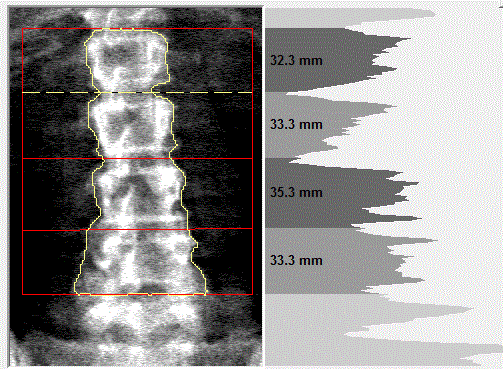

This radiograph shows the tantalum clips overlying L4 that are responsible for the black hole artifact on the Hologic lumbar spine scan.

This Hologic lumbar spine DXA scan shows a black hole-type artifact over L4. Items like lead bullets and tantalum clips show up as “black”on Hologic scans. The accompanying radiograph shows the clips over L4. L4 is omitted because of overlying artifacts.

Black hole artifacts occur with dense metals such as lead and tantalum on a Hologic scan. Other metals, like stainless steel, don’t produce black hole artifacts. Presumably there is complete attenuation of both Kev peaks so the difference is zero, making the image appear black. Lead bullets are measured as having high bone mineral content (BMC) and appear black in the dual-energy mode on the Hologic scanner and blue as artifact on GE Healthcare scanners. Black hole artifacts over bone are handled differently between Hologic and General Electric. With the Hologic scanner, when a dense artifact overlies bone, the BMC associated with that artifact is excluded, but the bone area is not altered. Consequently, the bone mineral density (BMD) of the affected vertebra, and of L1-4 is decreased. The GE scanners exclude both the associated BMC and area covered by the artifact, thereby minimizing the impact on BMD. Dense artifacts in the soft tissue do not significantly affect BMD on either manufacturer’s densitometer on phantom experiments., however, further experiments need to be done to verify this finding.